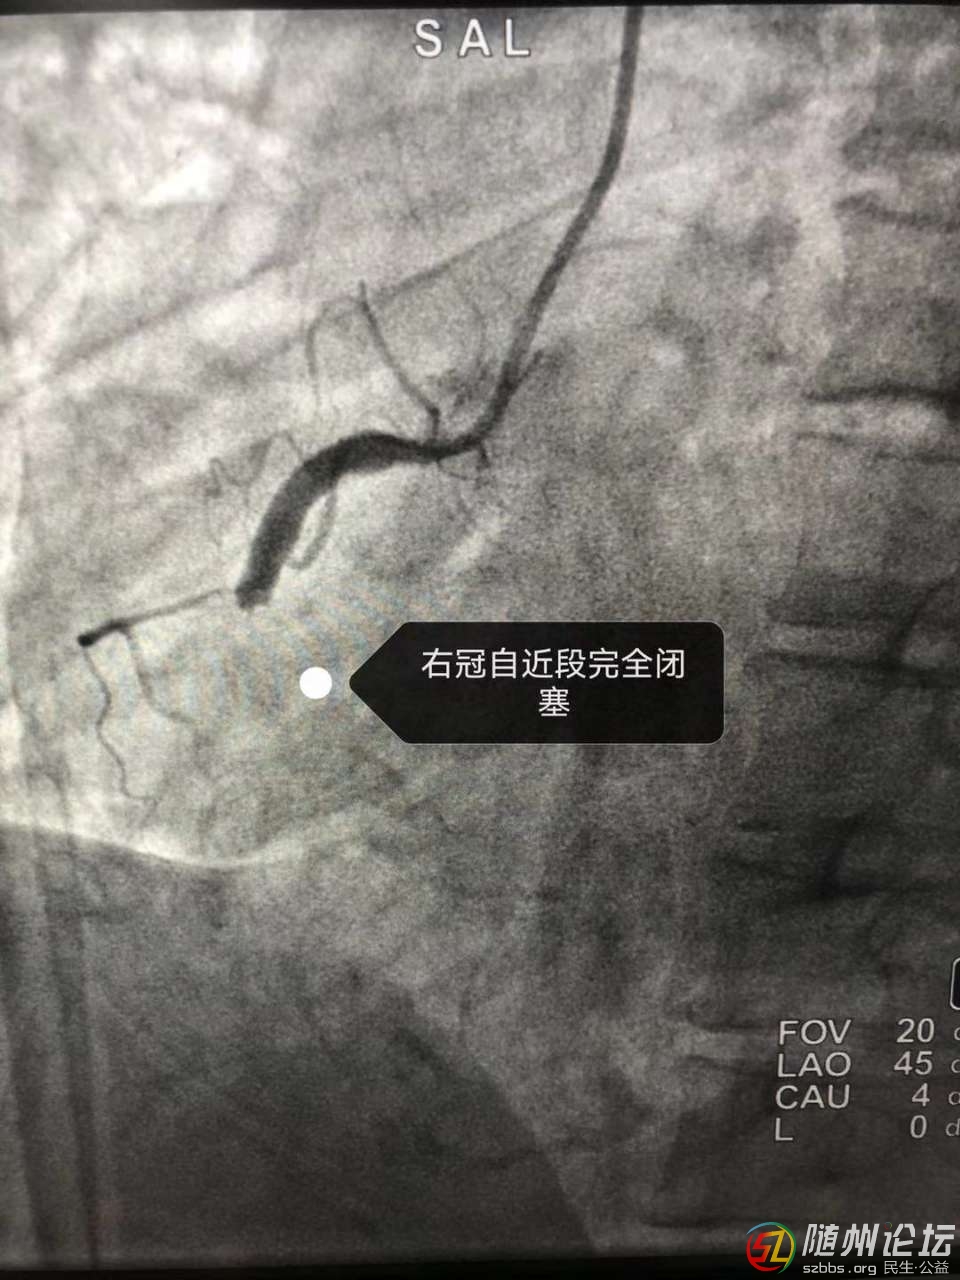

近日,隨縣中醫(yī)醫(yī)院上演了一場(chǎng)“生死時(shí)速”,成功救治1例急性心肌梗死患者,患者黃女士,46歲,在上班途中突發(fā)胸痛、胸悶、失語(yǔ)、持續(xù)不緩解,周圍人員撥打120后急診科出診 ...